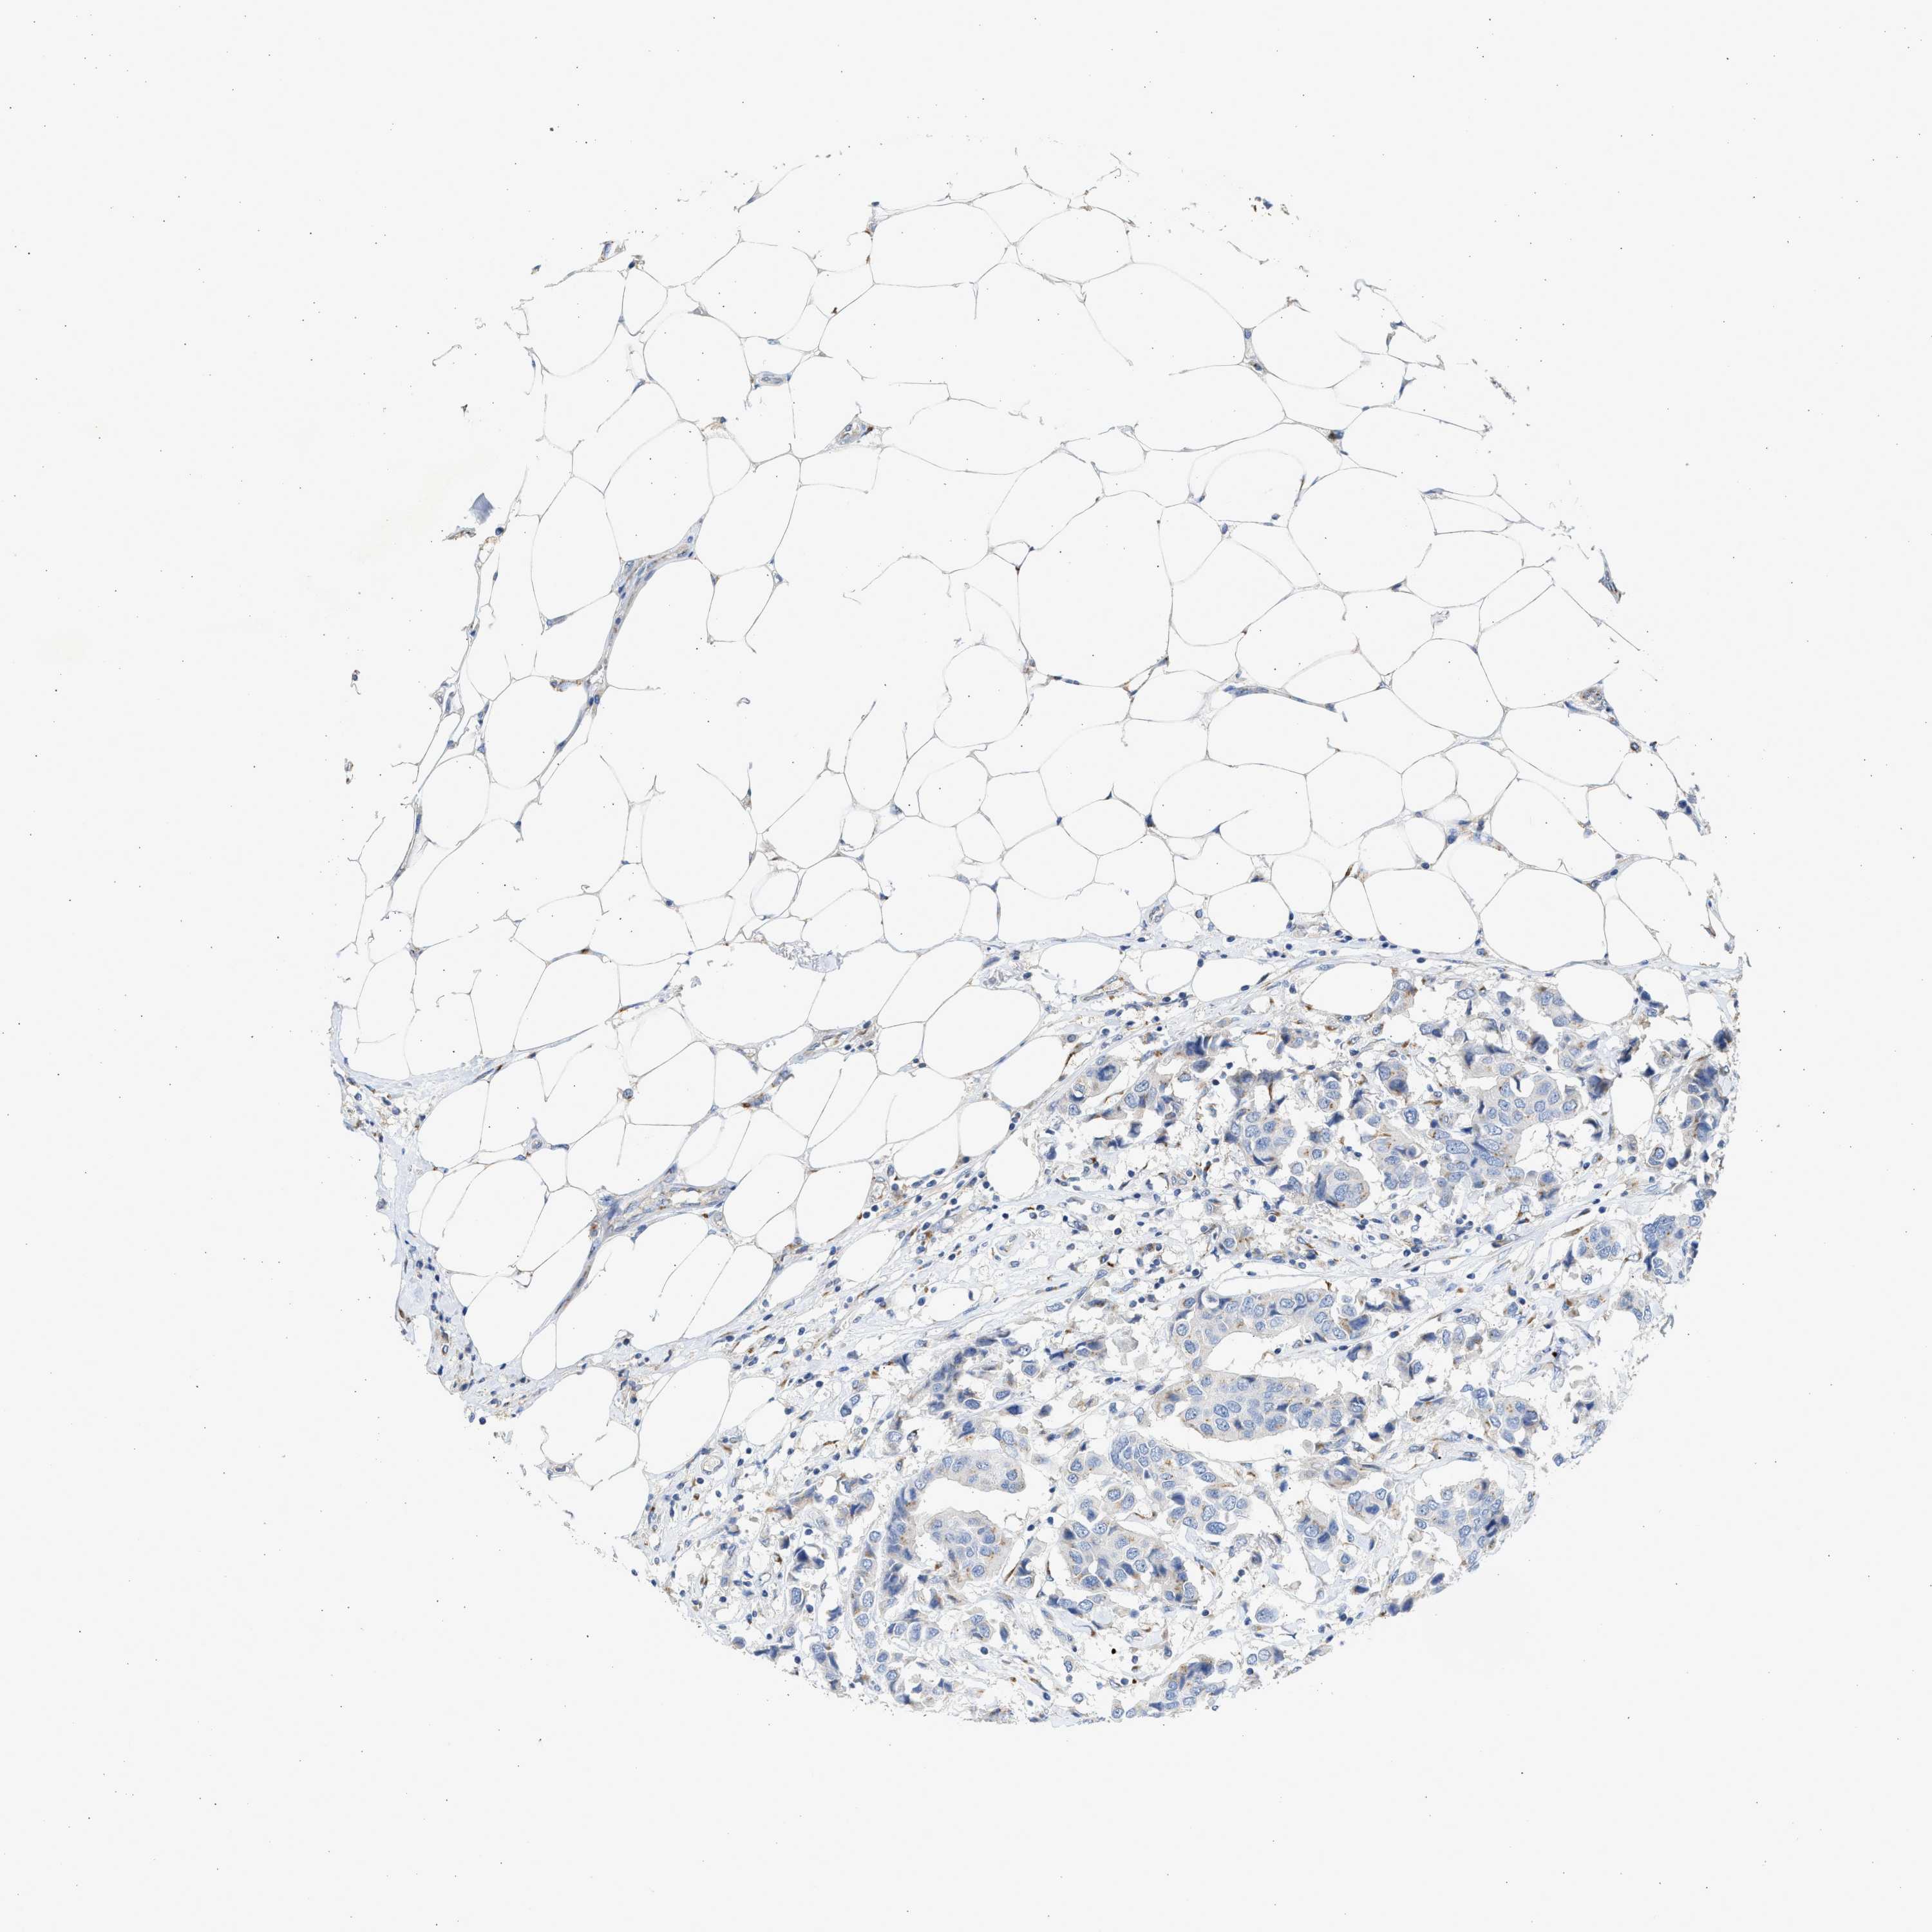

Breast cancer

Human cancer